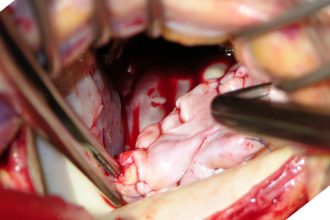

جراحه اصلاح الصمام الميترالي

تعتبر جراحه اصلاح الصمام الميترالي هي الحل الامثل…

تغيير صمامات القلب | أنواع الجراحات والخيارات المتاحة

تتعدد الأمراض والمشاكل التي يمكن أن تصيب القلب،…